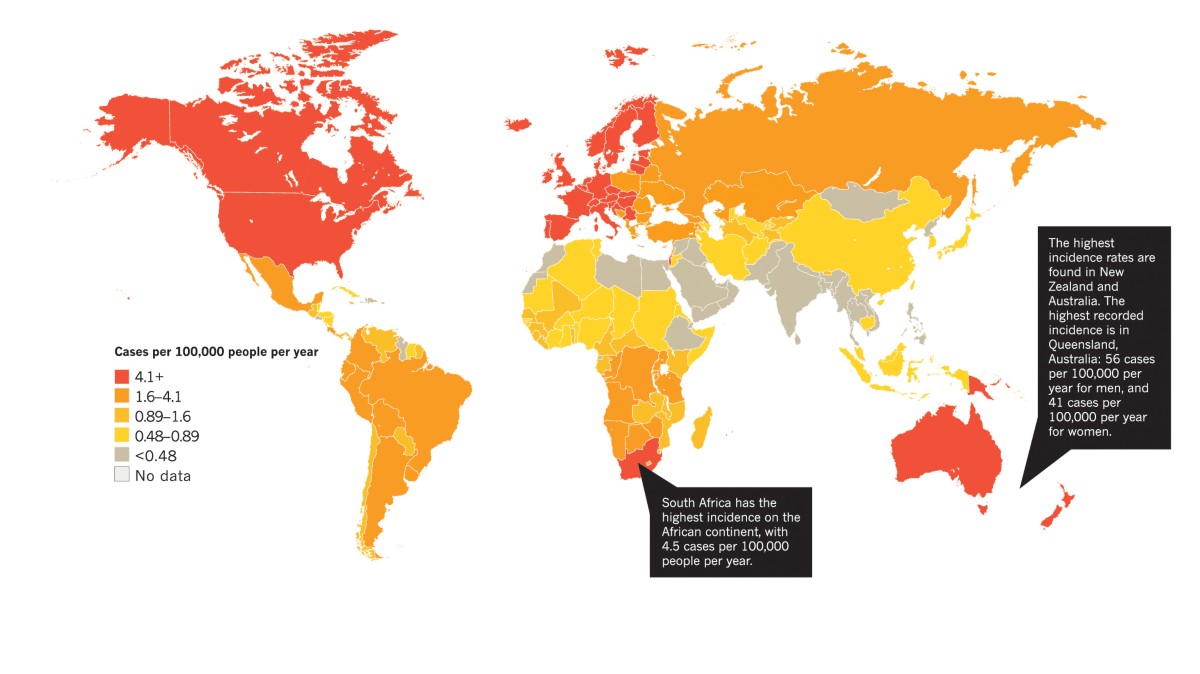

Main differences in UV protection habits in different countries and cultures.

Melanoma May: Why This Month Matters More Than You Might Think